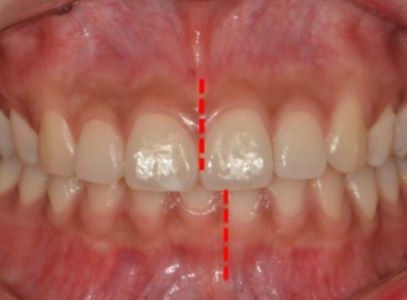

볼튼 비율 불균형으로 생긴 앞니 공간·총생 개선 사례